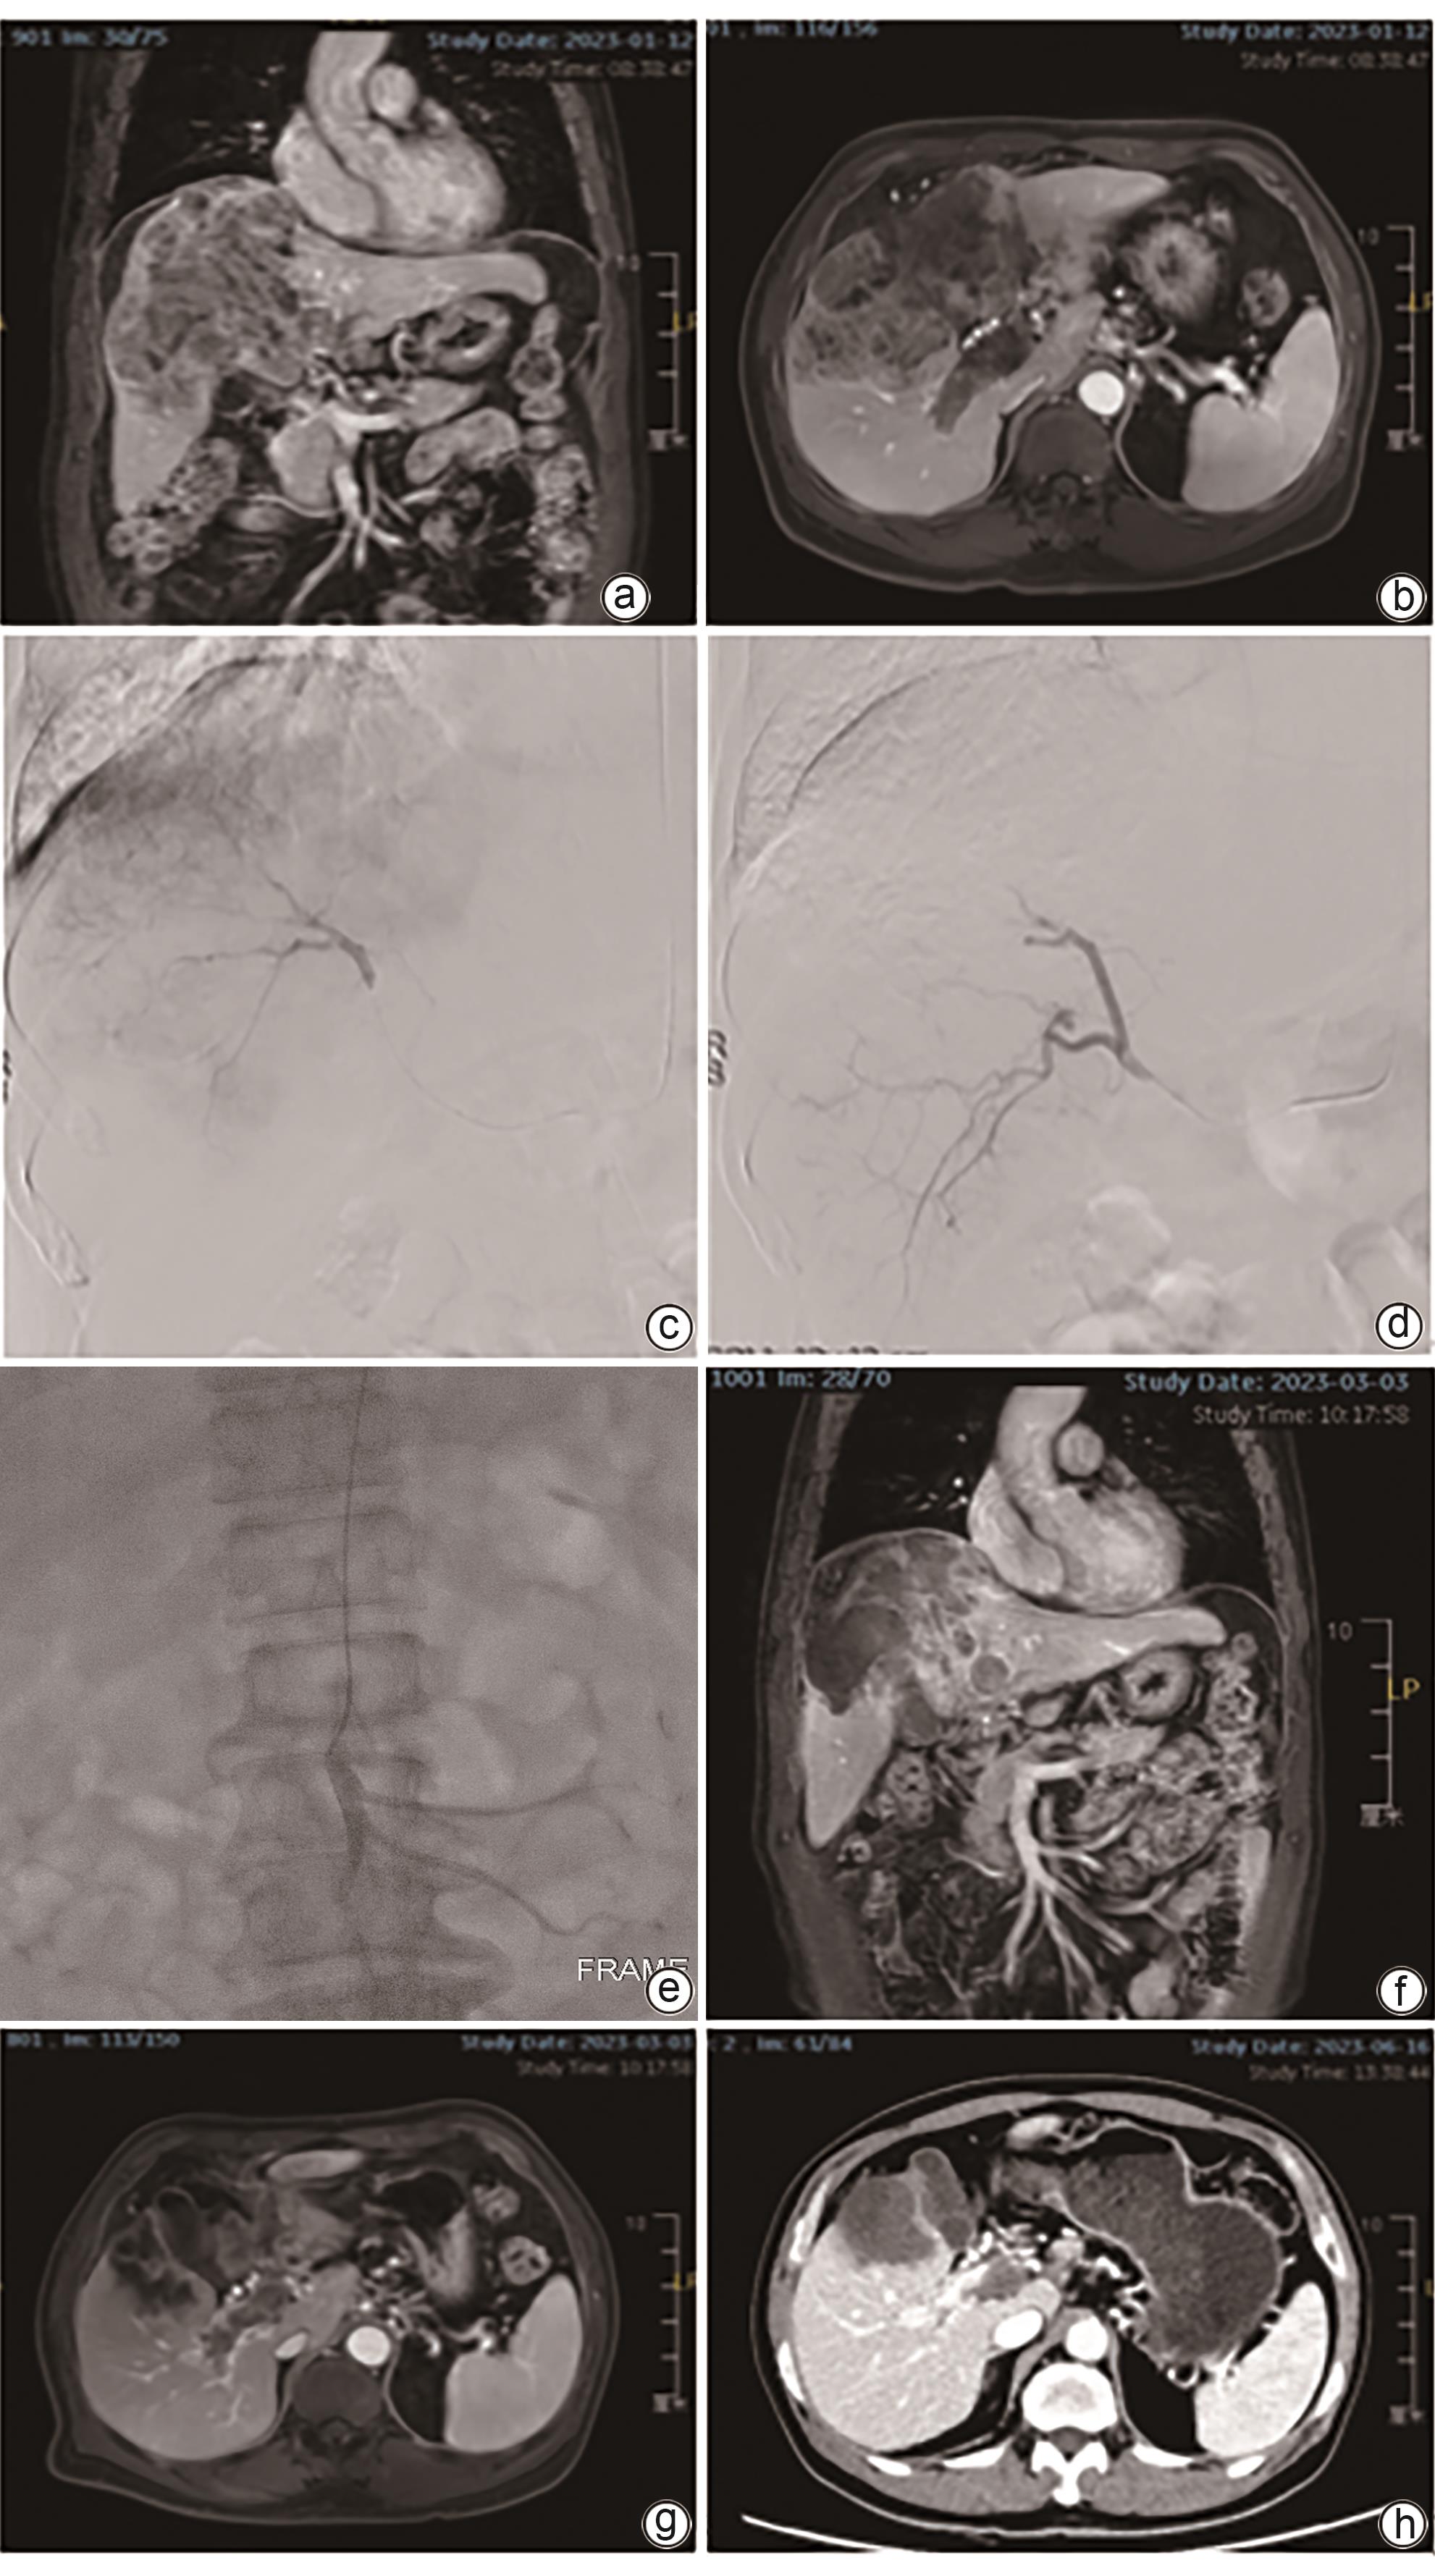

Efficacy of drug-eluting beads-transarterial chemoembolization combined with infusion chemotherapy via superior mesenteric artery in treatment of hepatocellular carcinoma complicated by portal vein tumor thrombus

Qianxin HUANG, Bin SHEN, Jinchang XIAO, Zhikang GAO, Duntao LYU, Yan LI, Hao XU, Qingqiao ZHANG

2024, 40(12): 2457-2463. DOI: 10.12449/JCH241216

Abstract(1465) HTML (329) PDF (1735KB)(68)

Abstract:

Objective  To investigate the efficacy of drug-eluting beads-transarterial chemoembolization (D-TACE) combined with infusion chemotherapy via superior mesenteric artery versus D-TACE alone in the treatment of hepatocellular carcinoma (HCC) complicated by portal vein tumor thrombus (PVTT).  Methods  A retrospective analysis was performed for the data of patients with HCC and PVTT who underwent interventional treatment in The Affiliated Hospital of Xuzhou Medical University from January 2022 to December 2023, among whom 15 patients received D-TACE combined with infusion chemotherapy via superior mesenteric artery and were enrolled as observation group, and after propensity score matching at a ratio of 1∶1, 15 patients who received D-TACE alone were enrolled as control group. Contrast-enhanced MRI of the upper abdomen was performed at 1, 2, and 3 months after surgery and every 3 months thereafter to evaluate the conditions of liver tumor and PVTT. Objective response rate (ORR) and disease control rate (DCR) were compared between the two groups. The independent-samples t test or the Mann-Whitney U test was used for comparison of continuous data between two groups, and the paired t-test or the Wilcoxon test was used for comparison of preoperative and postoperative data; the chi-square test was used for comparison of categorical data between two groups. The Kaplan-Meier curve was used to calculate the cumulative survival rate, and the Log-rank test was used for comparison between two groups.  Results  Both groups had a technical success rate of 100%, with no serious complications after surgery. The patients were followed up for 3-26 months (mean 10.5±6.7 months). At 3 months after surgery, there were no significant differences between the observation group and the control group in ORR (73.3% vs 53.3%, χ2=1.292, P=0.256) and DCR (93.3% vs 80.0%, χ2=1.154, P=0.283) for liver tumors, and compared with the control group, the observation group had significantly higher ORR and DCR for PVTT (ORR: 46.7% vs 13.3%, χ2=3.968, P=0.046; DCR: 100% vs 73.3%, χ2=4.615, P=0.032). The 3-, 6-, and 12-month cumulative progression-free survival rates were 93.3%, 86.2%, and 68.9%, respectively, for the observation group and were 80.0%, 62.2%, and 24.9%, respectively, for the control group (P=0.028), and the 3-, 6-, and 12-month cumulative overall survival rates were 100%, 88.9%, and 88.9%, respectively, for the observation group and were 93.3%, 85.6%, and 70.0%, respectively, for the control group (P=0.340).  Conclusion  Compared with D-TACE alone, D-TACE combined with infusion chemotherapy via the superior mesenteric artery shows better short-term efficacy in the treatment of HCC complicated by PVTT.